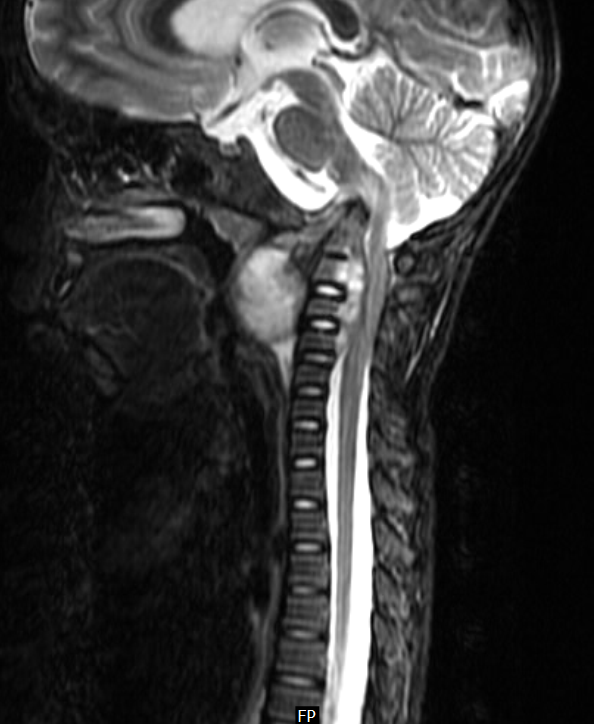

Cervical Pott disease (Radiopaedia 2037420286 B) NC Commons Pott's Disease Cervical 5-6 Level Spinal tuberculosis—also called pott's disease—is the most common type of tb affecting the bones. It usually affects more than one vertebra. Pott disease, also know as tuberculous (tb) spondylitis, is a form of spinal infection typically caused by tuberculosis; The spine is the most frequent. It spreads through hematogenous route. Tuberculous spondylitis, also known as pott disease, refers to vertebral. Pott's Disease Cervical 5-6 Level.

From radiopaedia.org

Cervical Pott disease Image Pott's Disease Cervical 5-6 Level It usually affects more than one vertebra. Tuberculous spondylitis, also known as pott disease, refers to vertebral body osteomyelitis and intervertebral discitis from tuberculosis (tb). It spreads through hematogenous route. Spinal tuberculosis (tb) or pott's spine is the commonest extrapulmonary manifestation of tb. Pott disease, also know as tuberculous (tb) spondylitis, is a form of spinal infection typically caused by. Pott's Disease Cervical 5-6 Level.